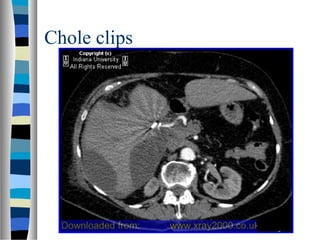

Chole clips